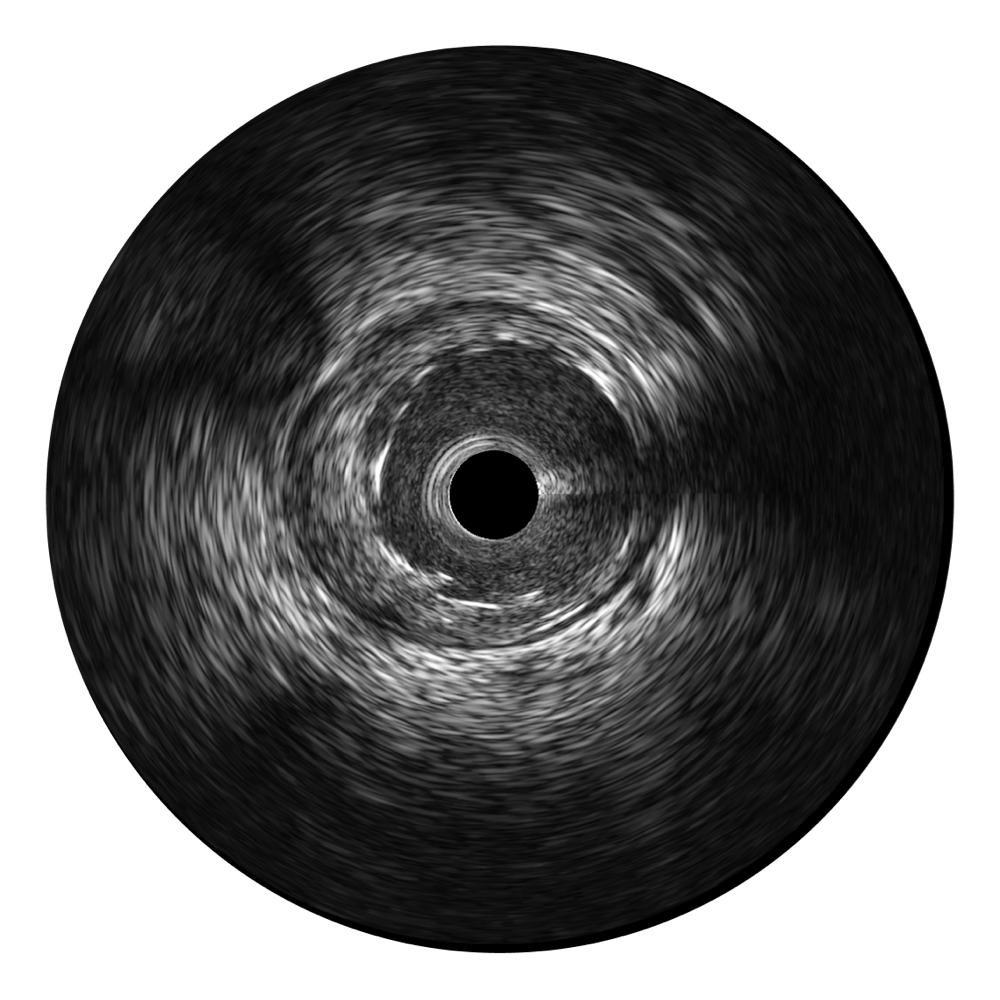

传统IVUS图像

对比传统IVUS导管成像,狗万官方网站宽频IVUS图像的近场支架梁显影更细腻,远场中膜外血管仍清晰可辨,兼顾远中近,兼顾分辨力与穿透深度